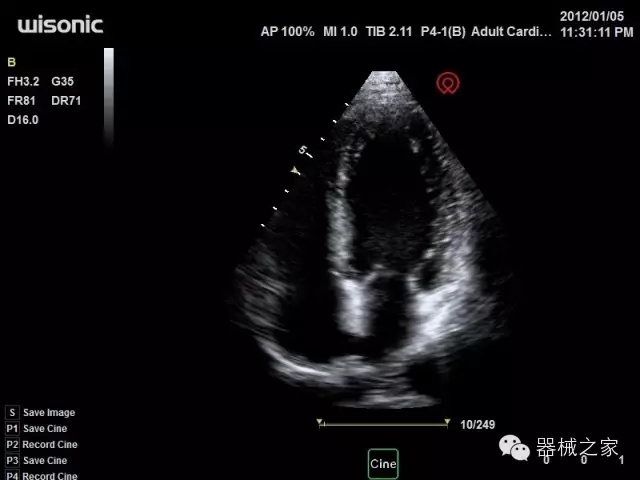

臨床圖片賞析

·全球目前唯一一款配備主機(jī)雙探頭接口,整機(jī)重量(含電池)在5公斤以內(nèi)的便攜式彩超;

·獨(dú)有的HoloTM PW 實(shí)時(shí)3取樣門PW成像技術(shù),精確進(jìn)行血管診斷;

·一鍵優(yōu)化B、Color、PW,Auto Doppler自動(dòng)識(shí)別血管位置、偏轉(zhuǎn)角度等,提高工作效率;

·30°超廣角精細(xì)偏轉(zhuǎn)成像技術(shù),更優(yōu)異的頻譜圖像;